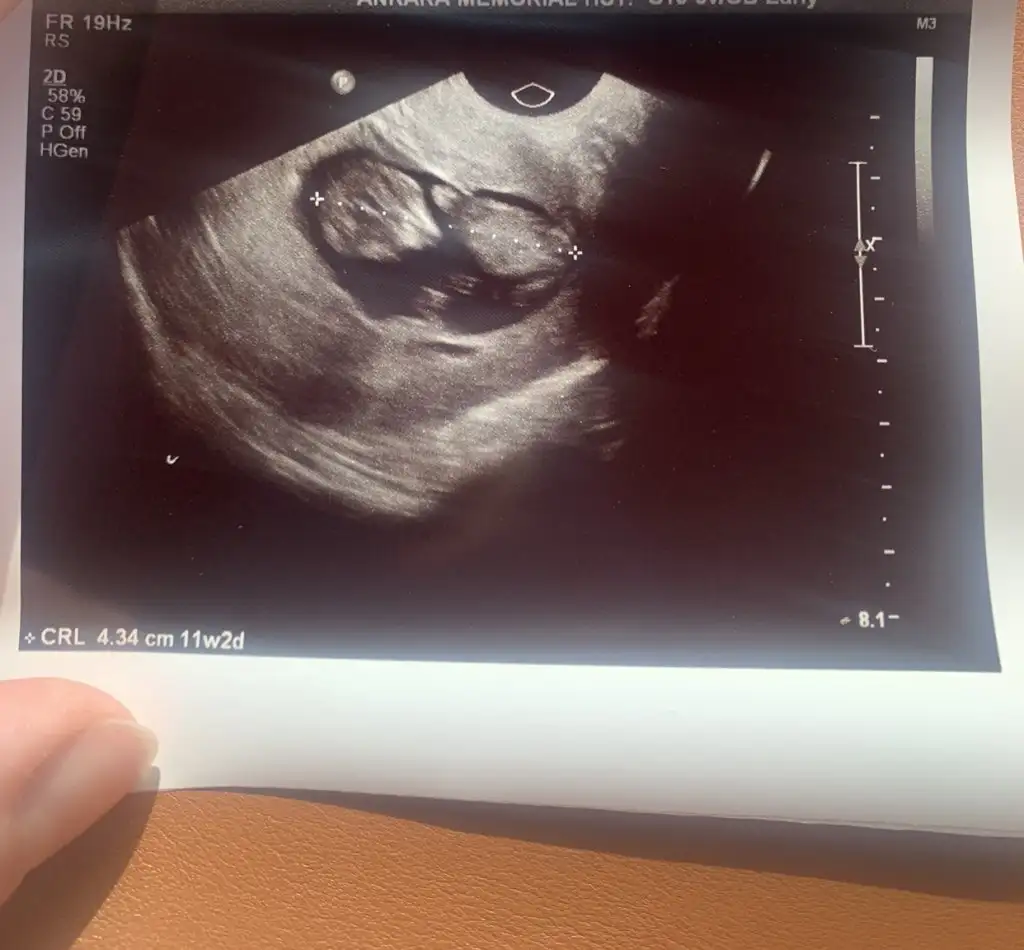

Merhaba, ben de bugün ikili taramaya gittim. Öğlen yemek yememe rağmen bebiş takla atıyorduKızlar ultrasona gitmeden çikolata yedim kahve içtim diyenler oluyor ya, bebeğin ultrasonda hareket etmesi daha mi iyi oluyor,ikili taramaya öyle mi gitsem

Gözün aydın canımMerhaba, ben de bugün ikili taramaya gittim. Öğlen yemek yememe rağmen bebiş takla atıyordudoktoru biraz zorladı fazla hareket etmesi ama herşeyini görebildi çok şükür cinsiyet için çok büyük ihtimal erkek dedi